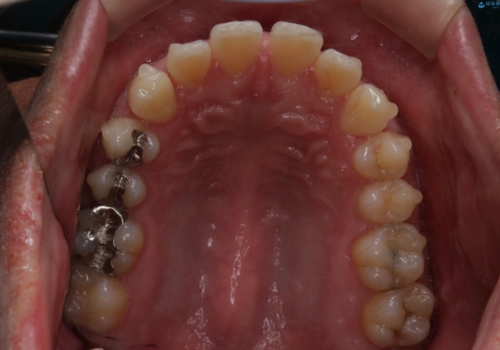

- 全体的に歯と歯の間に隙間があるのが気になるとのことで来院されました。インビザラインでの矯正治療をご希望されました。

隙間については、前歯と奥歯に多数あります。また、上下前歯は、外側に少し倒れているため隙間を閉じつつ、前歯を内側に引っ込めて並べることになりました。

インビザライン・ライトにて矯正治療を行うことになりました。